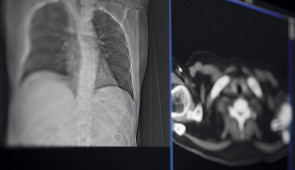

Chest CT scan images.